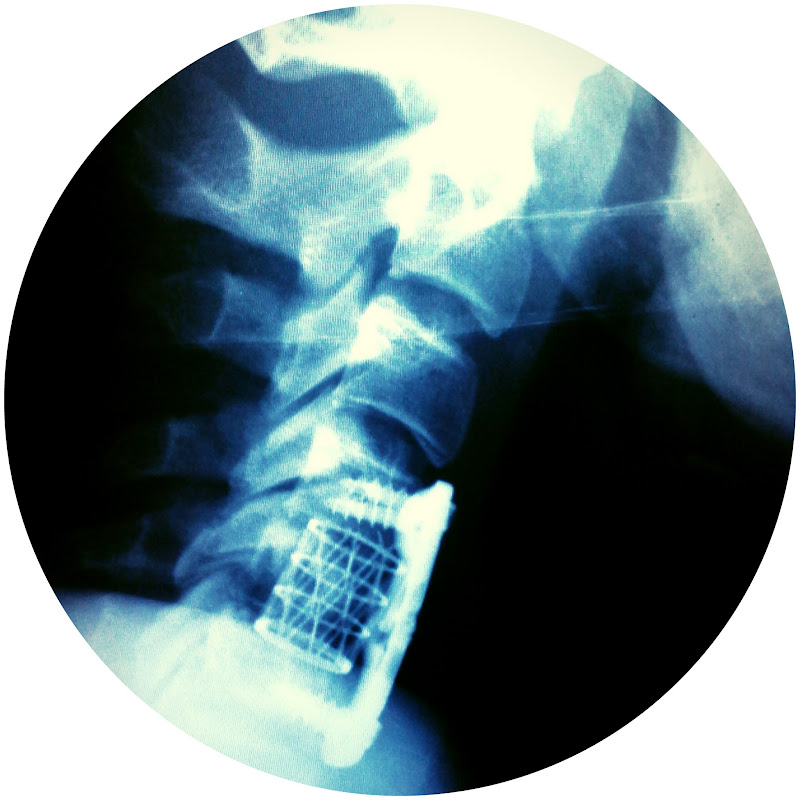

Трэйлер канала: 👣 КАК Я СЛОМАЛ ПОЗВОНОЧНИК И ЧТО ИЗМЕНИЛОСЬ. РАССКАЗ О СЕБЕ.

Ключевые слова: ″перелом позвоночника″ ″реабилитациция в домашник условиях″ ″инвалид колясочник″ ″доступная среда″ ″сломал позвончник″ ″позвоночник отдел″ шейник ″травма перелом″ ″восстановление после перелома позвоночника″ ″коченков александр″ спинальник shagvpered ″шаг вперед коченков″ coachenkov coachенков

Меня зовут Александр. С августа 2013г. я проявляю волю к победе над недугом: 11.08.2013 отдыхал на туристической базе. Увидел футбольные ворота и решил сделать на них упражнение - подъем с переворотом. Тяжелая металлическая конструкция оказалась не закреплена и рухнула вместе со мной. Придавив меня. В результате этого несчастного случая я сломал шею и стал неподвижен. Врачи говорили что не выживу. Но благодаря вашей помощи я живу и наслаждаюсь жизнью!